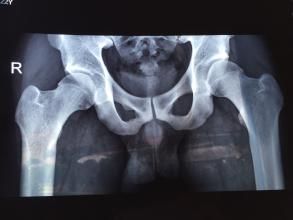

彈響髖髂脛束或臀大肌肌腱前緣增厚與外傷或勞損有關,外傷或勞損後受累組織充血水腫及無菌性炎症反應,導致纖維組織增生等一系列病理改變。有時增大的大粗隆上緣鉤住髂脛束後部而產生彈響;有時髖部彈響系由髂腰肌腱於髂恥結節上和/或髂前下棘上滑移所致;有時是於屈髖位時緊張的臀大肌下緣與坐骨磨擦而產生彈響;大粗隆骨軟骨瘤也可引起彈響髖。彈響髖病人常有髖內翻,由於股骨頸乾角變小,使得臀中肌和臀小肌力臂變短,外展功能受影響,這會增加髂脛束上部的張力,引起彈響和功能障礙。

彈響髖的診斷不難,檢查時令患者作患側髖關節的伸屈,內收或內鏇活動,在大轉子部聽到彈響,同時摸到或看到索狀物在大粗隆上滑移,就可確診。但需與關節內彈響相鑑別。